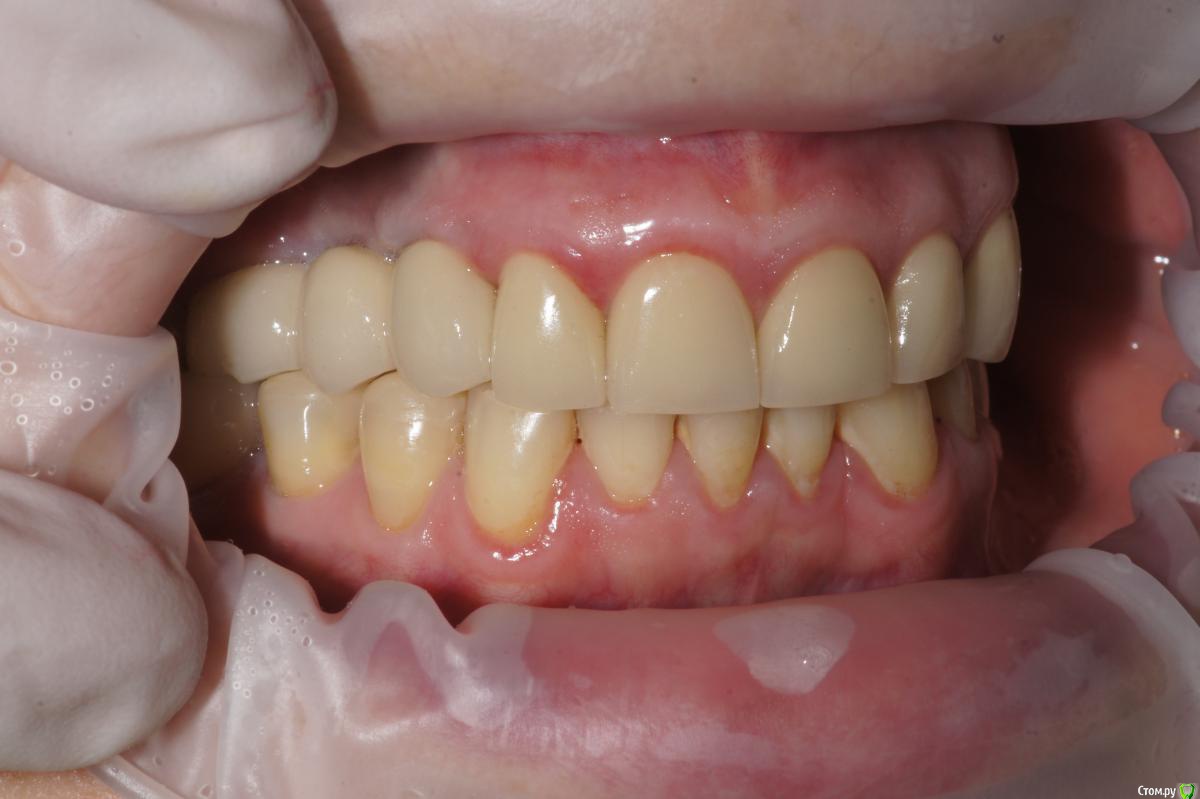

Alexandr_doc Опубликовано 21 сентября, 2018 Поделиться Опубликовано 21 сентября, 2018 Доброго всем времени! Пациентку протезировал доктор, которого уволили по ряду причин, обратилась ко мне на этапе после протезирования с жалобами на болезненность в области фронтальной группы зубов 1.2, 1.1, 2.1, 2.2, 2.3 при дотрагивании языком или пальцем. Перкуссия положительная как в вертикальном так и горизонтальном направлении. Установлены одиночные керамические коронки на каркасе из диоксида циркона. Отек, покраснение в области переходной складки отсутствует, также отсутствует болезненность при пальпации. Подвижность 1 степени. Прилагаю фотографии на этапе обращения. Ранее, на этапе протезирования было принято решение о депульпировании фронтальной группы тк присутствовала пульпитная симптоматика, после чего состояние улучшилось и остается стабильным по сей день. Предположил несколько причин оставшейся симптоматики: 1) несостоятельно проведенное эндо лечение - вариант отмел тк по прицельным снимкам и кт отсутсвуют очаги воспалительных процессов 2) некорректно изготовленные искуственные коронки ( глубокая поддесневая препаровка и агрессивный контур коронки ) 3) - окклюзионная перегрузка. Совместно с пацинеткой принято решение о снятии коронок во фронтальном отделе, была предупреждена о том, что возможно не получить хорошей динамики. С переменным успехом картина после нескольких корректировок временных коронок остается преждней. Болезненность на прежднем уровне, плюс по ходу наблюдения пришлось снять мост с опорой на уровне имплантатов, тк имели место быть воспалительные процессы в проекции имплантата 1.5. С удовольствием отвечу на все вопросы и приму любую критику. Ссылка на комментарий

Alexandr_doc Опубликовано 21 сентября, 2018 Автор Поделиться Опубликовано 21 сентября, 2018 Точно ли на кт нет изменений на корнях зубов? Мне на рентгеновских снимках что-то видится. жесткая каппа на верхний зубной ряд - я бы начал с этого.Нижние резцы устойчивы?Чем вам не нравится глубокая поддесневая препаровка? Десна выглядит также как и на интактных зубах НЧ.Как проверяется работа на предмет локальной перегрузки - не знаю, расскажите пожалуйста.На кт изменений нет, мне хотелось их найти, но нет. Мне будет не сложно сделать срезы и приложить их к посту, рассматривал некачественное эндо как один из первых причинных факторов. Жесткая капа какая? Какой дизайн и схему порекомендуете? Десна действительно сейчас выглядит также как и в других участках. При гипсовке в ЦС проверены: наличие первого контакта на фронтальной группе, проверена схема направляющих, распределение контактов на моделях. Ссылка на комментарий

kramer Опубликовано 26 сентября, 2018 Поделиться Опубликовано 26 сентября, 2018 Может, прозвучит банально, но нет смысла резцы вывести из окклюзии? По КТ плотный контакт с антагонистами Ссылка на комментарий

Alexandr_doc Опубликовано 26 сентября, 2018 Автор Поделиться Опубликовано 26 сентября, 2018 Я думаю в скором времени я буду вполне рассматривать варианты выведения зубов из окклюзии ( насколько это возможно ) или снятия коронок на некоторое время, например на день с колпачками из композита Ссылка на комментарий